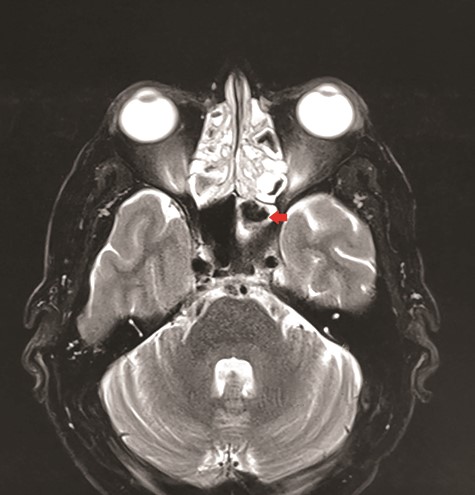

CT unveiled calcified densities within areas of hypoattenuation in the left sphenoid sinus. No marked bony destruction was observed (Fig. 2). A subsequent magnetic resonance imaging (MRI) was carried out to show hypodensity on T1 weighted post-contrast, and flow void in T2 weighted images within the same sinus (Figs. 3 and 4). Following informed consent, an emergency endoscopic left trans-ethmoidal sphenoidotomy was performed under general anaesthesia. A dense, darkened clay-like mass surrounded with the mucopurulent discharge was noticed within the left sphenoid sinus. The mucosa appeared inflamed and oedematous without clinical evidence of frank necrosis. The debris was utterly removed with a curette and sent for evaluation. The left sphenoid sinus was widened and thoroughly rinsed.

Axial view of MRI T2 weighted revealed flow void signal within the left sphenoid sinus.

Radiological modalities are deemed invaluable in the management of sphenoid FB [8]. Non-contrasted CT aids to delineate the bony structures of the paranasal sinus as well as to rule out other possible skull base pathologies. FB typically shows ‘hyperdense spot’ within a hypo attenuated paranasal sinus lining and is often associated with sclerosis of the adjacent bone [6, 7]. In contrast, acute invasive fungal sinusitis may demonstrate unilateral sinus opacification with soft tissue thickening and aggressive bony destruction [7]. MRI is useful to evaluate the surrounding soft tissue structures when involved. FB may present as hypointense in both T1 and T2-weighted owing to the absence of free water. Heavy metal depositions within the FB may reflect as a signal void in T2- weighted image [7]. Conventional dogman in the cure of a FB dictates a complete surgical removal of the lesion without the warrant of peri or post-operative antifungal treatment [1, 8]. Prognosis is generally good with a resolution of symptoms [2, 8].